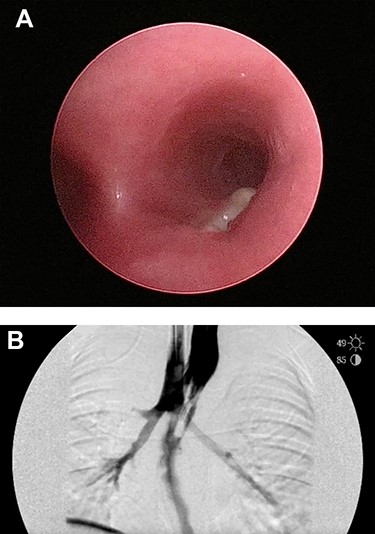

Six days later, repeat endoscopy was performed. A 1-cm area consistent with a broncho-esophageal fistula was seen on the posterior wall of the right mainstem bronchus just past the carina (Fig. 3A). Esophagram also clearly showed the fistula (Fig. 3B). A 10 French fenestrated nasogastric tube was placed such that the fenestrations were both above and below the fistula. Feeding jejunostomy tube was also surgically placed. The patient tolerated the procedure well and was able to transition to full feeds.

(A) Repeat bronchoscopy shows a broncho-esophageal fistula on the posterior wall of the right mainstem bronchus just past the carina. (B) Esophagram was performed while in the operating room and clearly shows the fistula to the right mainstem.